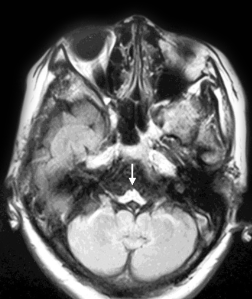

An additional imaging pattern characterized by bilateral symmetric hyperintensity on T2-weighted imaging involving the central inferior olivary nucleus, the pyramids, and the cuneate and gracile fascicles, with sparing of the peripheral inferior olivary nucleus and inferior peduncle (termed the “chipmunk sign”), is a common feature in people with Alexander disease regardless of age of onset.62